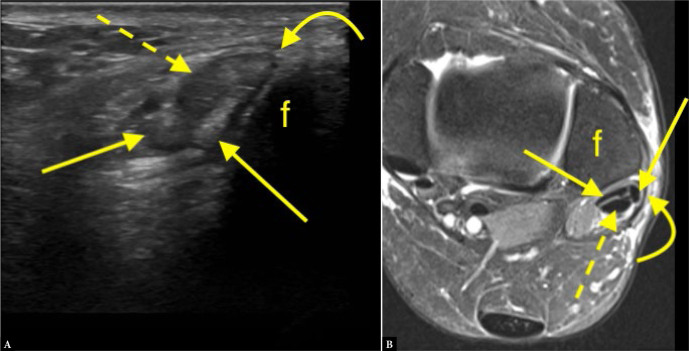

Aim: The purpose of this study was to evaluate the diagnostic value of ultrasound compared to magnetic resonance imaging (MRI) as a reference in detecting peroneus brevis split ruptures.

Material and methods: We re-reviewed 112 ultrasound examinations performed between 2020 and 2021 by three musculoskeletal radiologists with 8-10 years of experience. Patients were referred due to pain lasting at least 8 months in the posterolateral ankle. Ultrasound was performed using a LOGIQ E9 General Electric device with a 6-15 MHz or 18 MHz probe. Sixty-three patients who underwent MRI within 8 months and were included in the study. Ultrasound and MRI findings were categorized as: a) no peroneus split, b) presence of peroneus split, or c) unspecific findings. MRI served as the reference standard. Sensitivity, specificity, positive predictive value, negative predictive value, and accuracy were calculated.

Results: Seven cases (11.1%) were false positives (diagnosed on ultrasound but not MRI) and 9 (14.3%) were false negatives (missed by ultrasound but detected on MRI). Six cases (9.5%) were true positives (identified on both ultrasound and MRI), and 41 patients (65.1%) were true negatives (negative on both modalities). Ultrasound showed a sensitivity of 40.0% and specificity of 85.4%. The positive predictive value (PPV) was 46.2%, while the negative predictive value (NPV) was 82.0%.

Conclusions: Ultrasound demonstrated limited sensitivity but high specificity in detecting peroneus brevis split ruptures.